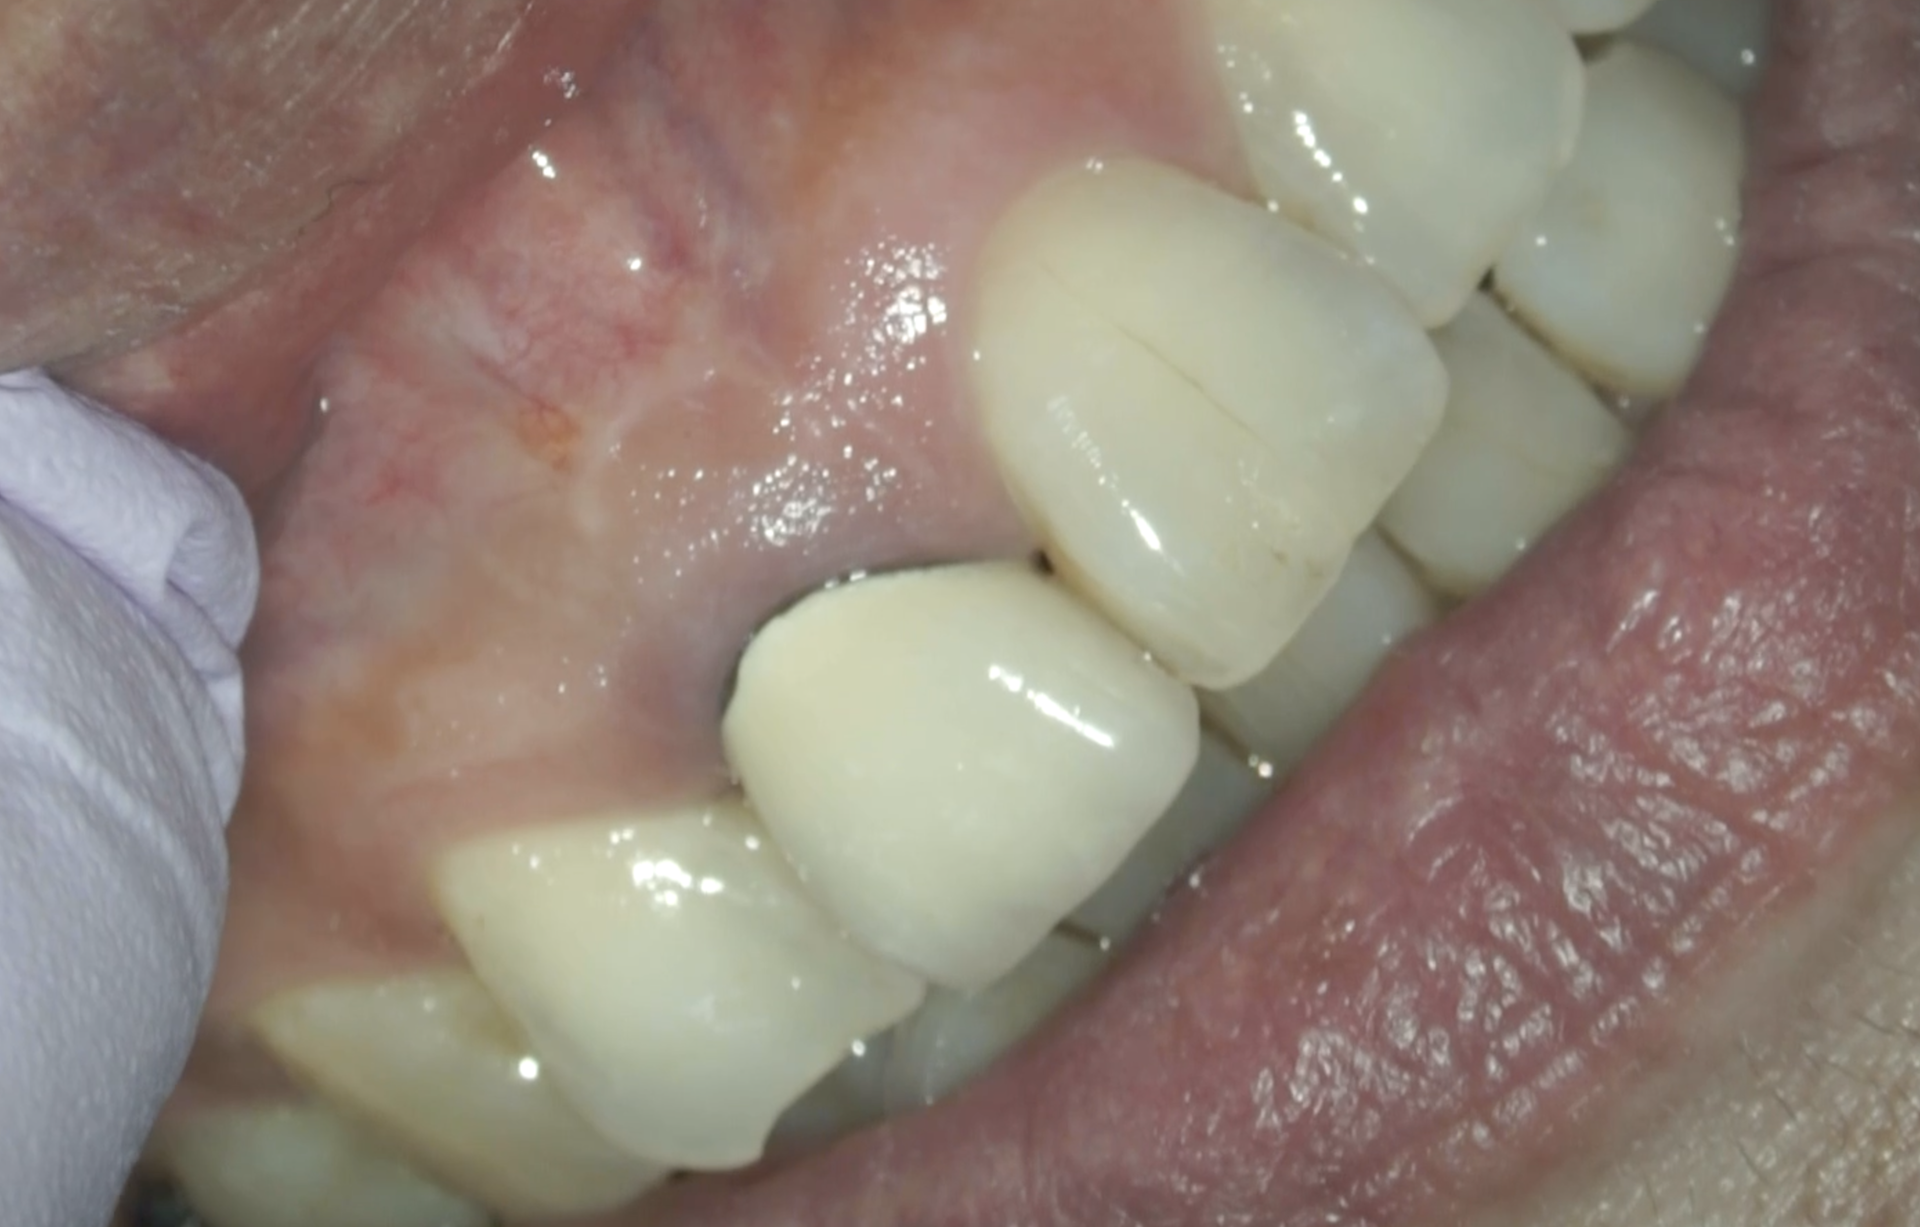

術前のSinus tract, 圧痛は消失した。

また、Submarginal Flapのオペ後の瘢痕は、ほぼ目立たないレベルであった。